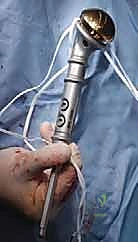

3. الاستئصال الجذري والمفاصل الصناعية الخاصة بالأورام (Tumor Endoprosthesis)

في حالات التدمير الواسع جداً للعضد القريب (قرب الكتف) أو العضد البعيد (قرب الكوع)، أو في حالة النقيلة الوحيدة التي تتطلب استئصالاً جذرياً (En-bloc resection) لضمان عدم عودة الورم:

* يقوم الدكتور محمد هطيف باستئصال الجزء المصاب من العظم بالكامل مع الورم المغلف به ككتلة واحدة، بهوامش أمان سليمة.

* يتم استبدال العظم والمفصل المستأصل بـ مفصل صناعي ضخم خاص بالأورام (Modular Megaprosthesis). هذه المفاصل مصنوعة من التيتانيوم والمعادن المتقدمة، وتأتي بقطع قابلة للتركيب لتناسب الطول الدقيق للعظم المفقود.

* هذه الجراحة تتطلب مهارة فنية عالية جداً لإعادة خياطة العضلات والأوتار (مثل أوتار الكفة المدورة في الكتف) في المفصل الصناعي لضمان عودة حركة الذراع.